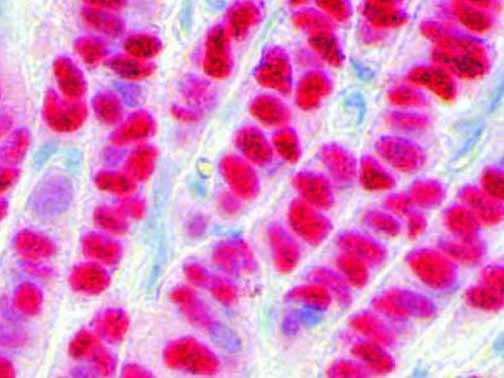

The first cytokines released are interleukin 1β (IL-1β) and tumor necrosis factor-α (TNF-α), which attract a variety of circulating white blood cells (WBCs) to the infection site, including neutrophils, monocytes, macrophages, and natural killer (NK) cells. This response, along with the antipathogenic chemicals released by these cells (i.e., complement), comprise the innate immune response. These cells directly attack the invading pathogen and also release additional cytokines, chief among them interleukin-1 and 6 (IL-6). IL-6 is essential for invoking the adaptive immune response, which calls T-cells, B-cells, and T helper (Th) cells to the infection site. IL-6 also stimulates further recruitment, proliferation and activation of macrophages.

It is the ICU physician who is most likely to witness one of the deadliest manifestations of the abnormal immunological response, the cytokine storm syndrome (CSS). This response is also referred to by some as the cytokine release syndrome (CRS). CSS is characterized by continuous activation and expansion of macrophage and lymphocyte populations, which secrete large amounts of cytokines, causing the cytokine storm. This massive cytokine release is akin to hemophagocytic lymphohistiocytosis (HLH) disease, a syndrome characterized by initial unchecked and persistent activation of cytotoxic T lymphocytes and NK cells.